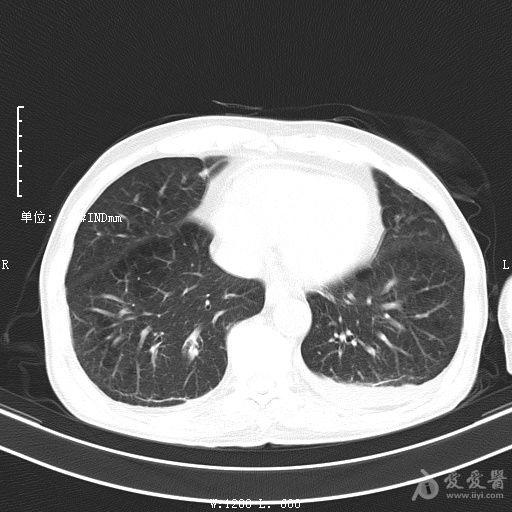

最新的肺炎疫情形勢嚴(yán)峻,病毒變異使得防控工作更加復(fù)雜,許多地方出現(xiàn)了新的病例,甚至有些地區(qū)的疫情出現(xiàn)了反彈,這不僅是對醫(yī)療系統(tǒng)的考驗,更是對每一個生命的考驗,我們需要密切關(guān)注疫情動態(tài),共同應(yīng)對這場挑戰(zhàn)。??